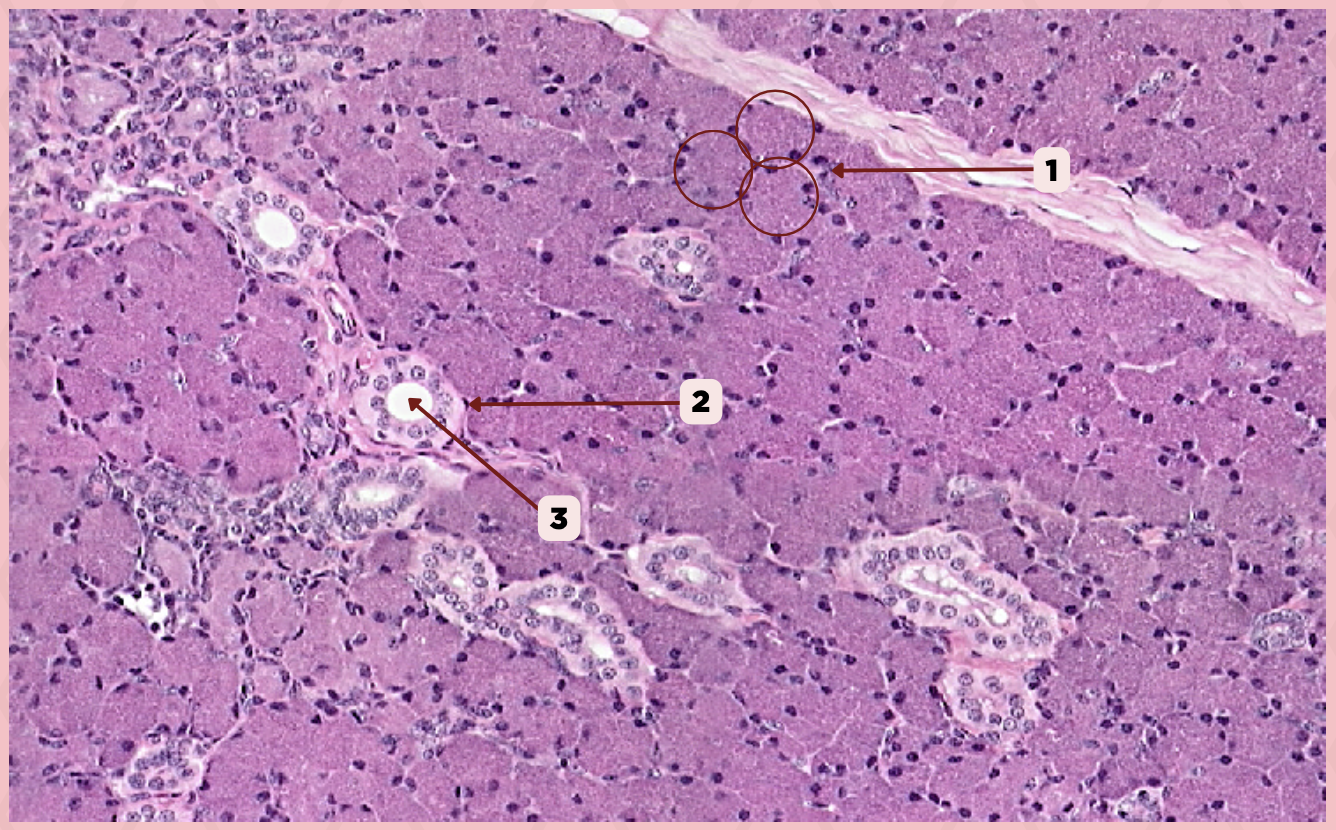

Parotid

Identify the specimen.

Capsule

Identify the structure labeled as 1.

Septa

Identify the structure labeled as 2.

Lobule

Identify the structure labeled as 3.

Lymph Node

Identify the structure labeled as 4.

B) Interlobular Ducts

A duct within lobules with stratified cuboidal epithelium in the initial segment and stratified columnar epithelium in the proximal segments.

A) Striated Ducts

B) Interlobular Ducts

C) Intercalated Ducts

Parotid

Identify the specimen.

Vein

Identify the structure labeled as 1.

Artery

Identify the structure labeled as 2.

Nerve

Identify the structure labeled as 3.

Interlobular Septa

Identify the structure labeled as 4.

Interlobular Duct

Identify the structure labeled as 5.